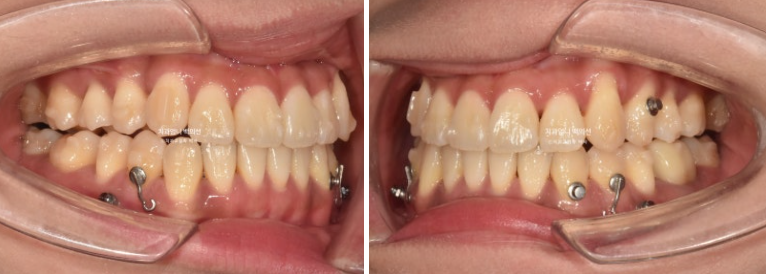

왼쪽 송곳니 하나가 완전히 배열에서 벗어나 있습니다.

덧니가 있으면 덧니쪽으로 중심선이 쏠리기 마련입니다.

위 앞니 중심선이 덧니쪽으로 틀어져 있는 것이 보입니다.

앞니는 윗니가 아랫니를 덮지 못하고 거꾸로 물리는 반대교합과 절단교합이 보입니다.

이 경우 입을 다물때 아랫입술이 나와보이고 입매가 부자연스럽습니다.

23.09~25.03

초진 3mm의 중심선 불일치가 해결되었습니다.

윗니가 아랫니를 덮는 양이 안정적입니다.

잘 내려와준 덧니입니다.

앞니가 거꾸로 물리던 부분도 정상교합을 찾았습니다